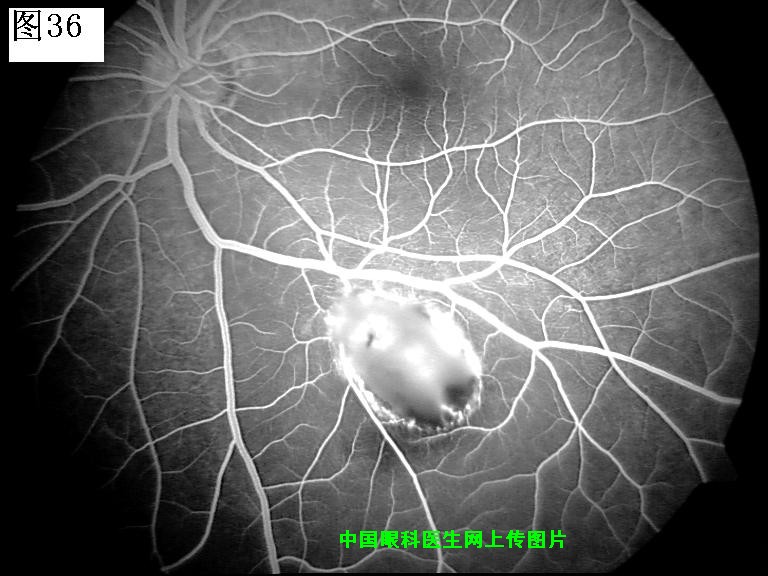

33 34 35 36